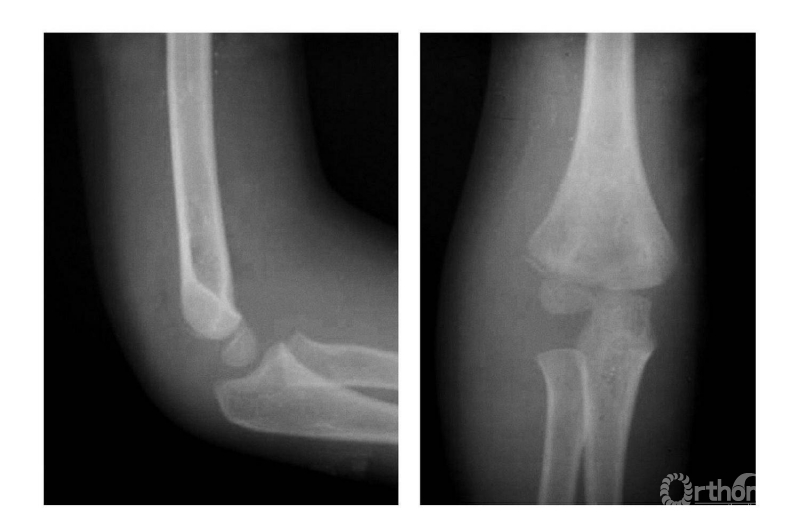

一、无移位型

例:仅见骨折线通过干骺端(图1)。

图1